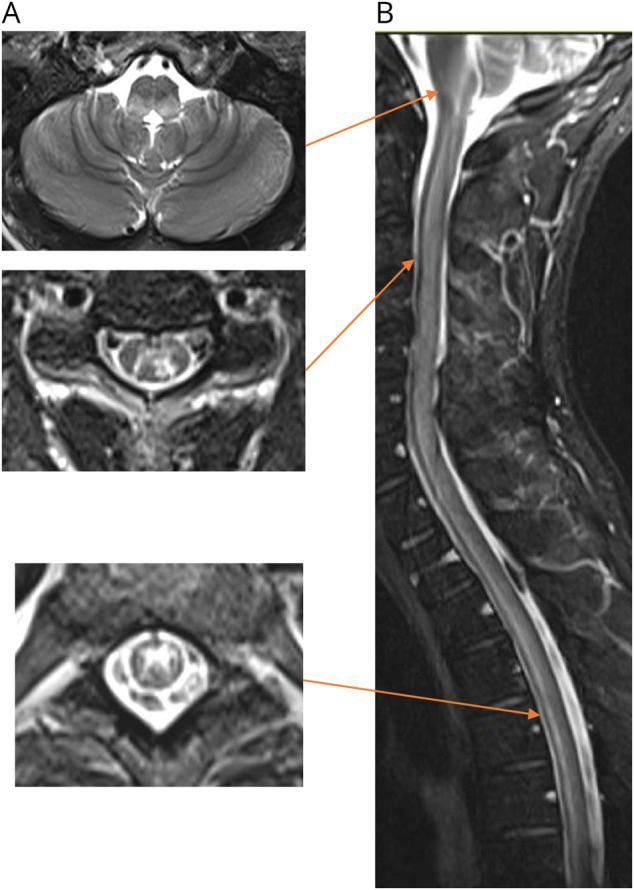

RESULTS

Of 238 patients identified by EMR query, 197 were excluded (148 not meeting prespecified inclusion criteria, 49 had typical MS), resulting in 41 patients for review. The mean age at myelitis onset was 44 ± 15 years; 39 (95%) were female. Rheumatologic diagnoses included 17 (41.5%) with systemic lupus erythematosus (SLE), 10 (24.3%) Sjögren syndrome (SS), 6 (15%) undifferentiated connective tissue disease (UCTD), 5 (12%) combinations of SLE/SS/UCTD with antiphospholipid antibody syndrome, 1 (2.4%) rheumatoid arthritis, 1 (2.4%) psoriatic arthritis, and 1 (2.4%) Behçet disease. 20 patients (49%) were diagnosed with AQP4-IgG seropositive NMOSD, 3 (7%) with MOGAD, and 18 (44%) had "double-seronegative" myelitis. Of these 18, 3 were diagnosed with AQP4-IgG seronegative NMOSD, 1 neuro-Behçet disease, and 14 other (unclassifiable) myelitis. Excluding 1 patient with neuro-Behçet disease, 18 (90%) of 20 AQP4-IgG seropositive patients had longitudinally extensive cord lesions compared with 5 (29%; < 0.001) of 17 "double-seronegative" patients and 2 (67%) of 3 with MOGAD. "Double-seronegative" patients more commonly had CSF-restricted oligoclonal bands. Functional outcomes did not differ by diagnosis, and most patients received acute immunotherapy at the time of initial myelitis diagnosis with at least partial recovery over a median follow-up of 38 (interquartile range: 9-74) months.

通过 EMR 查询,共确定了 238 例患者,其中 148 例不符合预设纳入标准,49 例患有典型 MS,排除了 197 例患者,最终有 41 例患者进行了回顾。脊髓炎发病时的平均年龄为 44±15 岁;39 例(95%)为女性。风湿性疾病诊断包括 17 例系统性红斑狼疮(SLE)、10 例干燥综合征(SS)、6 例未分化结缔组织病(UCTD)、5 例 SLE/SS/UCTD 合并抗磷脂抗体综合征、1 例类风湿关节炎、1 例银屑病关节炎和 1 例贝赫切特病。20 例(49%)患者被诊断为 AQP4-IgG 阳性 NMOSD,3 例(7%)为 MOGAD,18 例(44%)为“双阴性”脊髓炎。在这 18 例中,3 例被诊断为 AQP4-IgG 阴性 NMOSD、1 例神经贝赫切特病和 14 例其他(未分类)脊髓炎。排除 1 例神经贝赫切特病患者后,20 例 AQP4-IgG 阳性患者中有 18 例(90%)存在纵向广泛的脊髓病变,而 17 例“双阴性”患者中仅有 5 例(29%;<0.001)和 3 例 MOGAD 患者中仅有 2 例(67%)存在这种情况。“双阴性”患者更常见脑脊液寡克隆带受限。功能结局与诊断无关,大多数患者在初次脊髓炎诊断时接受了急性免疫治疗,在中位数为 38(四分位距:9-74)个月的随访中至少有部分恢复。